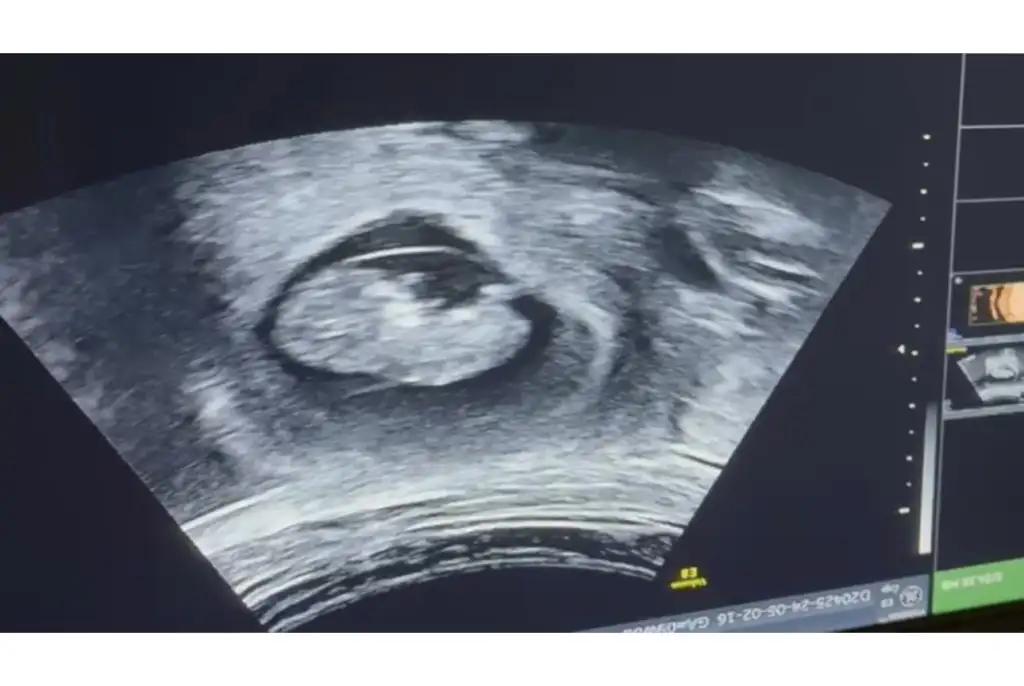

Banada bakar mısınız lütfenMerhaba canım nuba göre erkek duruyor

Sanki çıkıntısı var erkek gibi duruyorBanada bakar mısınız lütfen

Ama çok erkek gibi duruyo yaBuda bugünün ultrasonu doktor kız dedi ama gören erkek diyor sizce ne